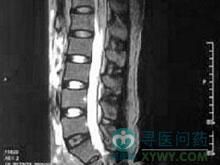

(1)脊髓MRI 病變動靜脈畸形血管內有流空現象,可有脊髓萎縮,有時能在T2像看到高信號。

主要基於以上的臨床表現及影像學檢查。脊髓MRI顯示局部擴張血管內有流空現象,可有脊髓萎縮,有時能在T2像看到高信號。脊髓血管造影能明確診斷。